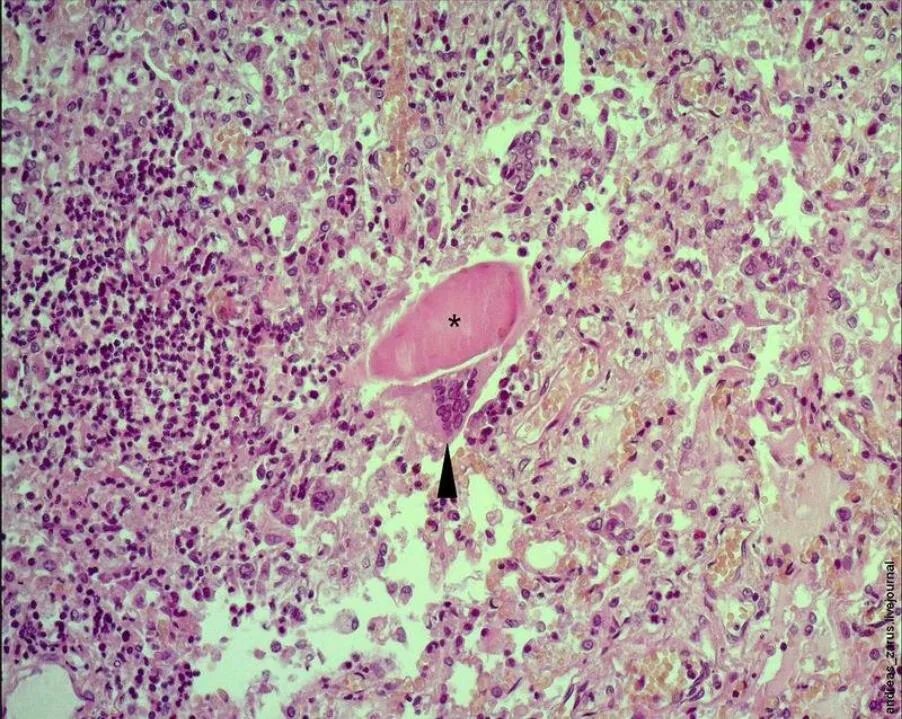

Клетка типа инородных тел